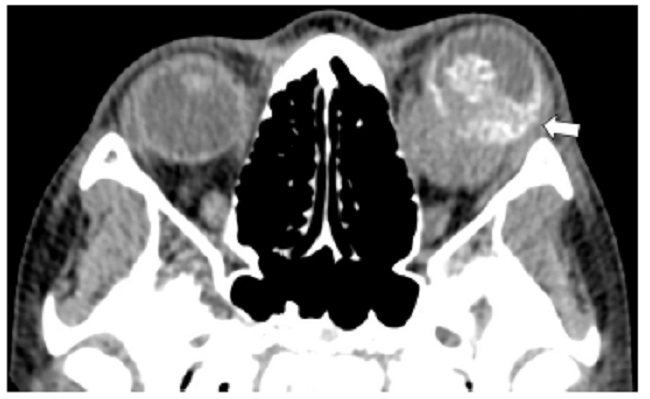

Las calcificaciones oculares y el material médico se pueden confundir con cuerpos extraños u otras lesiones orbitarias1. Las localizaciones típicas de las calcificaciones permiten diferenciarlas de cuerpos extraños hiperdensos. Las más frecuentes son las calcificaciones trocleares, las placas esclerales, las drusas del nervio óptico y la ptisis bulbi. Las primeras tienen localización superomedial dentro de la órbita (Fig. 13), en la tróclea del músculo oblicuo superior, aunque se pueden observar en todas las edades, hay mayor prevalencia de calcificaciones trocleares en pacientes con enfermedades autoinmunes y niveles elevados de fosfatasas alcalinas. Las placas esclerales se localizan en los sitios de inserción de los músculos rectos medial y lateral (Fig. 14) y son más comunes en los pacientes ancianos. Las calcificaciones que ocurren cerca del disco óptico se conocen como drusas del nervio óptico (Fig. 15), las cuales se asocian a degeneración macular y pueden ser causa de pseudopapiledema benigno. La ptisis bulbi es una atrofia y calcificación del globo ocular como secuela de enfermedades infecciosas, inflamatorias o traumáticas previas (Fig. 16) (1,11. Los imitadores de lesiones abiertas del globo ocular incluyen las deformidades como coloboma, estafiloma y el globo ocular elongado por glaucoma o miopía (Fig. 17). Las masas orbitarias y los hematomas también pueden alterar el contorno del globo ocular y asociarse a calcificaciones o relacionarse con desprendimiento de retina (Fig. 18) (1,6,8,11.

Los cambios postratamiento y los dispositivos orbitarios también pueden malinterpretarse como patologías traumáticas. Dentro de estos cambios se incluyen la faquectomía con reemplazo del cristalino, las hebillas esclerales (Figs. 19 y 20), las inyecciones intraoculares de aceite de silicona, la retinopexia neumática y las prótesis de globo ocular1,6,11. Para diferenciar la silicona intraocular de hemorragia se ha propuesto la medición de las UH, siendo la atenuación > 100 UH sugerente de silicona y < 90 UH de sangre11 (Fig. 20).